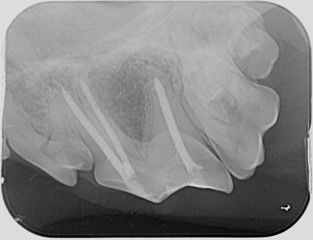

Fractured tooth following standard root canal placement

Root canal with final restoration